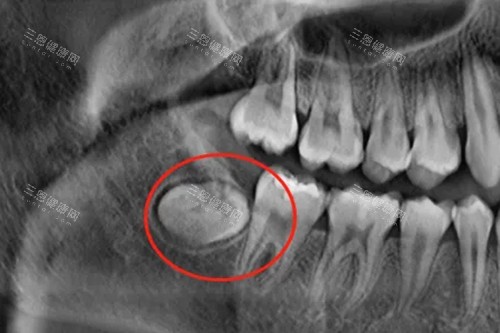

阻生齿的破坏力则堪称“多面手”!它可能是“邻牙杀手”——与第二磨牙之间形成“卫生死角”,引发龋齿、牙髓炎;可能是“颌骨破坏者”——长期刺激周围组织,形成含牙囊肿甚至颌骨骨髓炎;还可能是“美貌杀手”——导致牙列拥挤、咬合紊乱,让脸型变丑。更可怕的是,阻生齿引发的感染可能扩散至全身,引发脓毒血症等致命并发症!

阻生齿的治疗则更“果断”!除非位置极深、与重要神经血管关系密切,否则医生通常会建议预防性拔除。这是因为阻生齿就像“潜伏的特工”,平时可能没症状,但一旦“暴动”(如抵抗力下降时),就会引发剧烈疼痛和感染。更关键的是,随着年龄增长,阻生齿周围的骨质会越来越硬,拔除难度和风险也会增加——20岁拔阻生齿可能10分钟搞定,40岁可能得花1小时,还容易损伤邻牙!

机构差异化亮点:北京协和医院口腔科引入“智能化导板拔牙技术”,通过CT扫描+3D打印,能精细定位阻生齿的牙根走向和邻牙关系,将手术创伤降低50%,术后肿胀反应减轻70%。该技术尤其适合复杂阻生齿(如倒置阻生、骨埋伏阻生)的患者,网友反馈“拔完牙当天就能吃面条,完全不像传说中那么恐怖”。